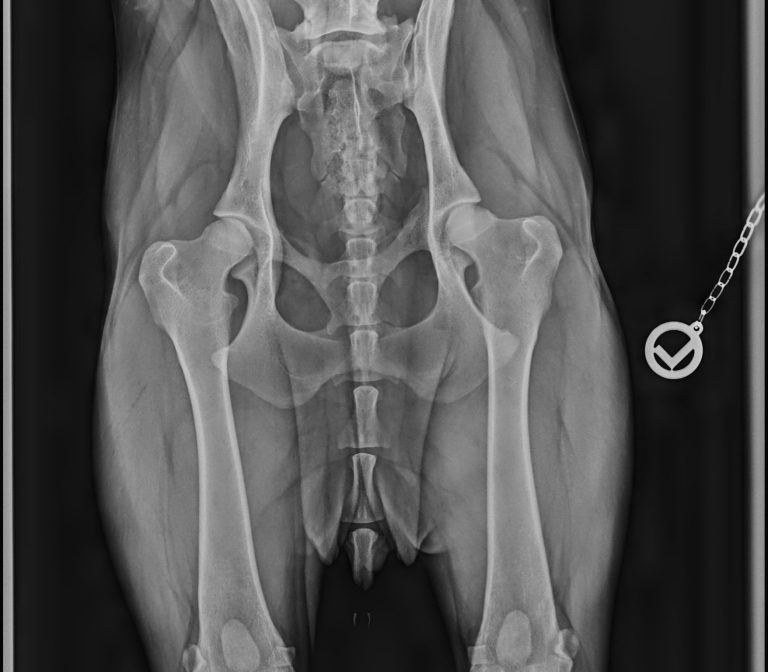

- • Gangbildanalyse

- • Bewegungscheck

- • individuelle Einschätzung